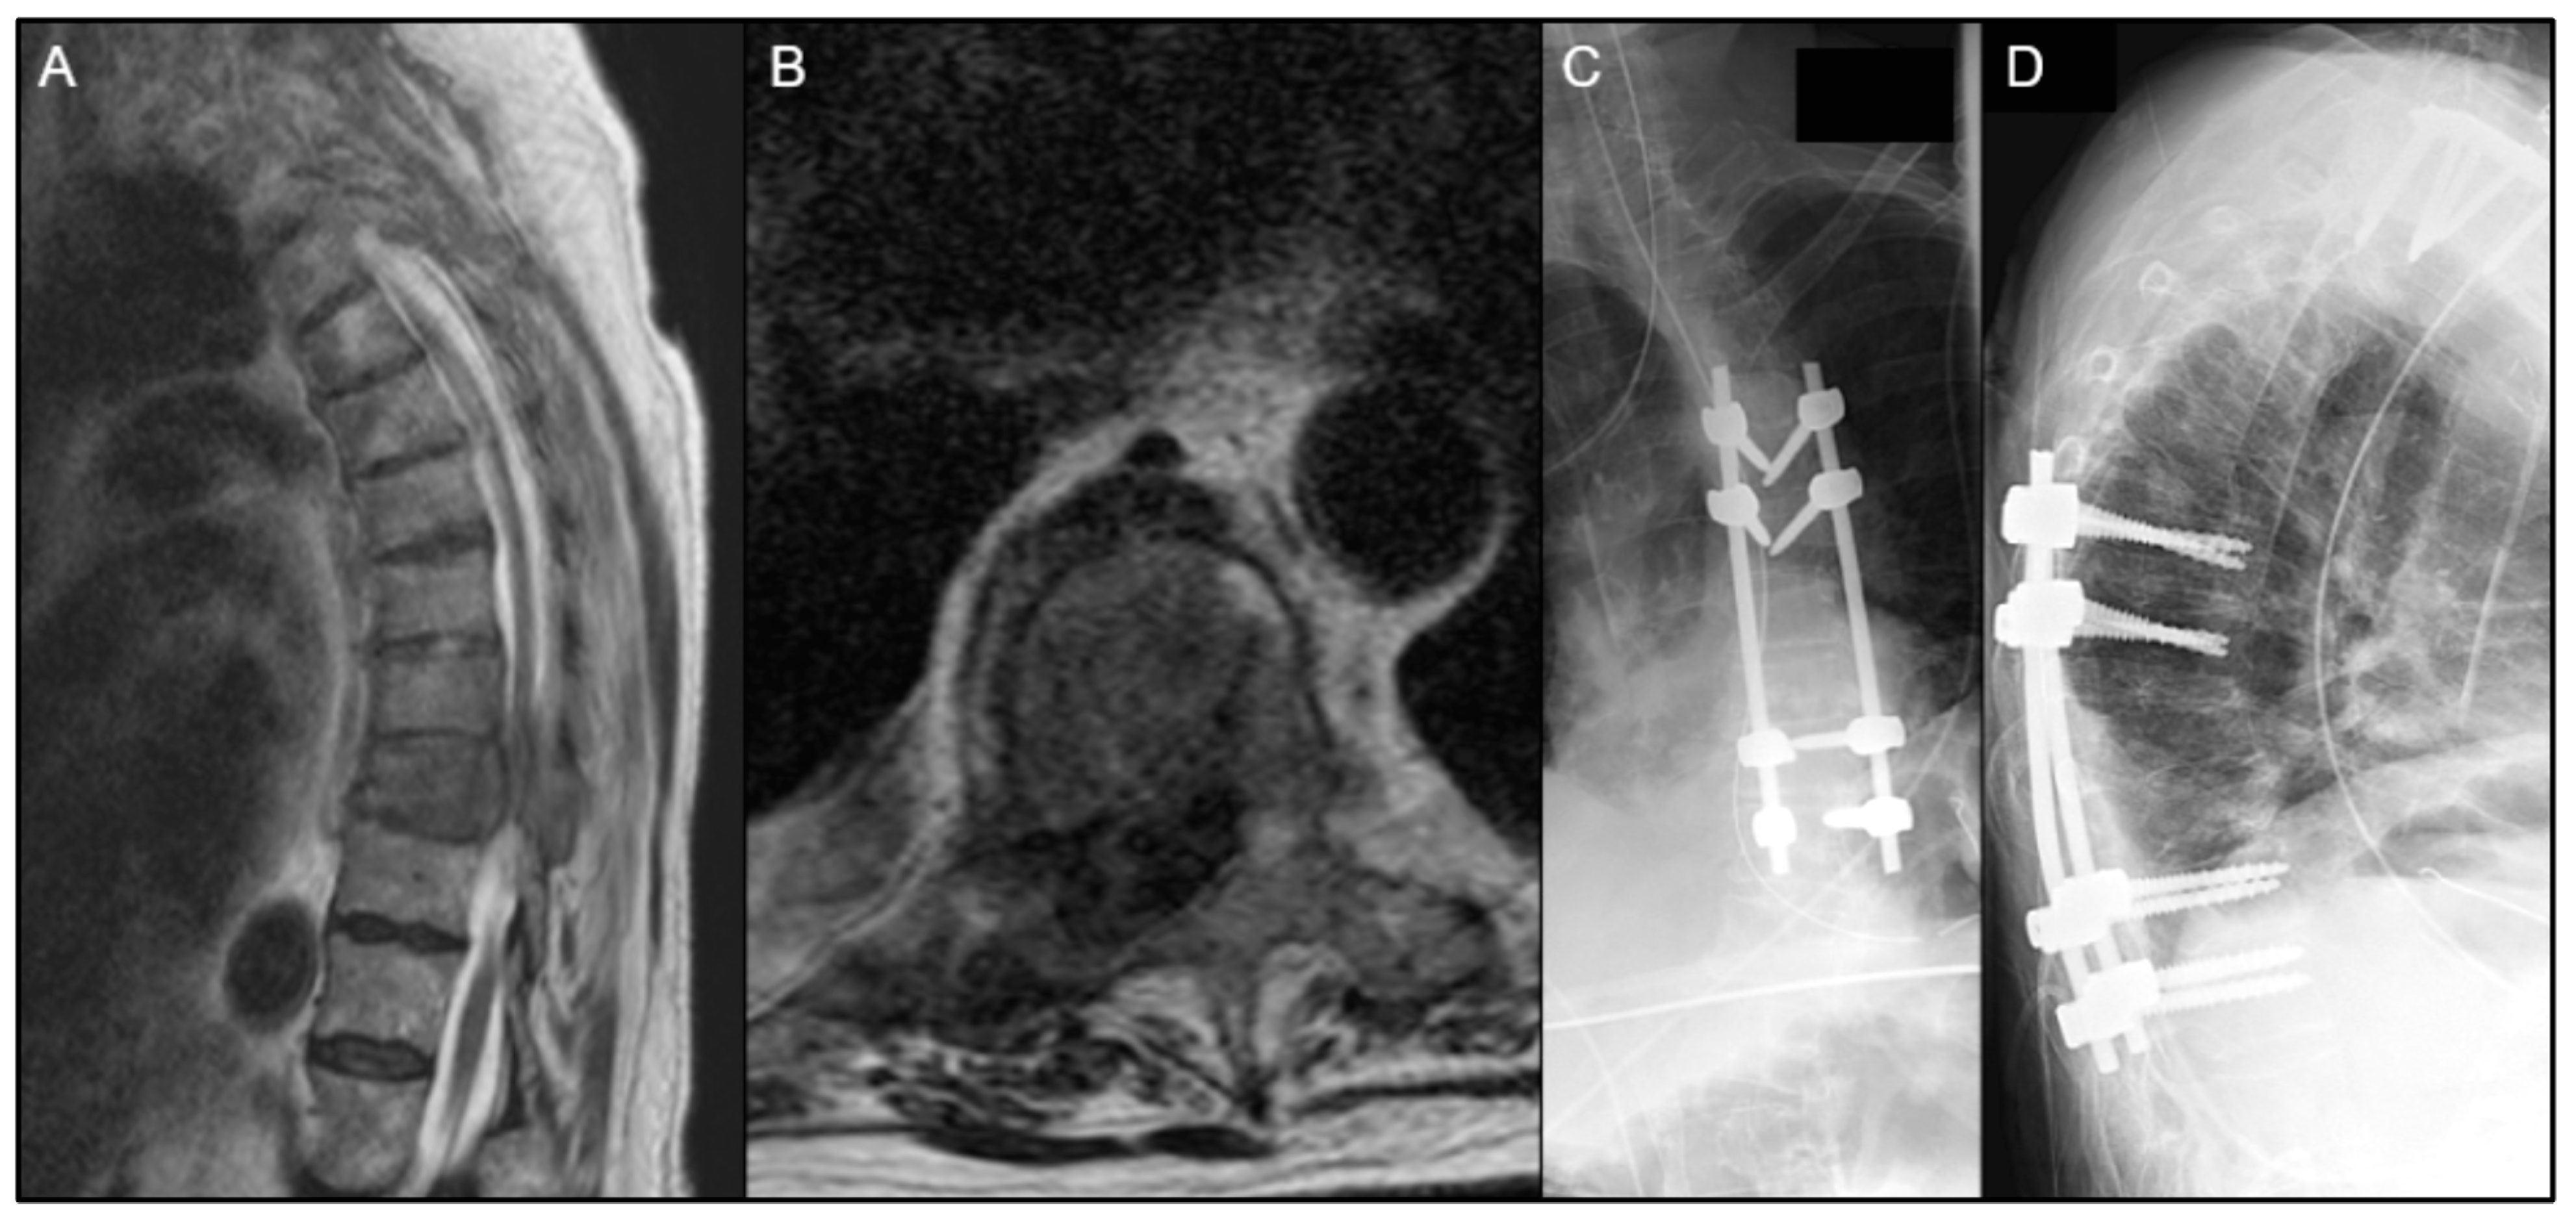

| Patient | Age/Sex | Primary Organ | Instrumented Levels | Radiation | Time to Wound Complication | Reoperation for Wound Complication |

|---|---|---|---|---|---|---|

| 1 | 58M | RCC | T10-L2 | Preop RT only | 48 days | No |

| 2 | 69M | Prostate ADK | T2-T9 | Preop RT only | 39 days | Yes |

| 3 | 44M | Lung ADK | T5-T9 | Postop EBRT | 14 days | Yes |

| 4 | 56F | Lung ADK | O-C5 | Postop EBRT | 22 days | Yes |

| 5 | 72M | Lung ADK | T1-T6 | Postop SBRT | 21 days | Yes |

| 6 | 52M | Lung ADK | C5-T5 | Postop EBRT | 22 days | Yes |

| 7 | 55M | Lung neuroendocrine | T5-T10 | No RT | 43 days | Yes |

| 8 | 67F | Unknown carcinoma | T11-S1 | No RT | 155 days | No |

| 9 | 74F | Lung neuroendocrine | T11-L3 | No RT | 22 days | Yes |

| 10 | 68F | Leiomyosarcoma | L3-S1 | No RT | 23 days | Yes |

| 11 | 75M | Adenocarcinoma | L1-L3 | No RT | 45 days | Yes |

| 12 | 65F | Thyroid | L4-S1 | No RT | 20 days | Yes |

| 13 | 68M | Lung ADK | L1-L3 | No RT | 84 days | Yes |

| 14 | 63M | Squamous-cell carcinoma/ENT | C7-T9 | No RT | 32 days | Yes |

| 15 | 65M | Melanoma | L1-L4 | No RT | 7 days | No |

| 16 | 56M | Squamous-cell carcinoma/ENT | T8-T10 | No RT | 8 days | Yes |

| 17 | 56F | RCC | T7-T11 | No RT | 46 days | Yes |